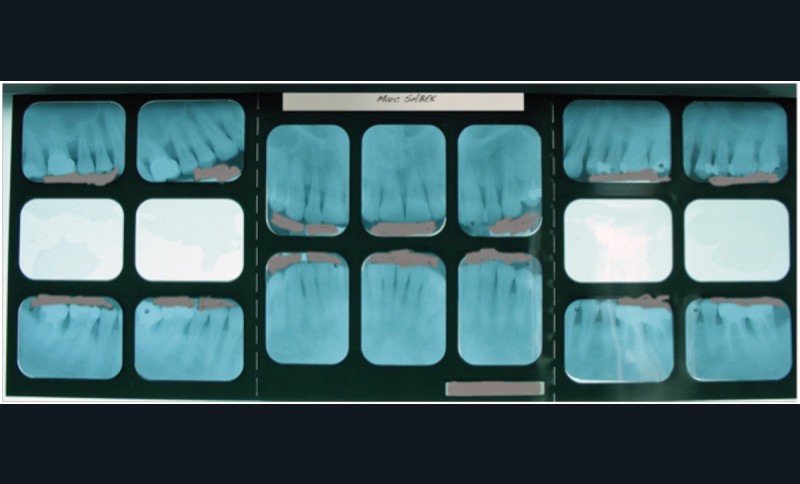

• Pour un status complet des arcades dentaires, HBQK041, « Radiographies intrabuccales rétroalvéolaires et/ou rétrocoronaires de 14 secteurs distincts de 1 à 3 dents contiguës » et 111,72 € d’honoraires opposables.